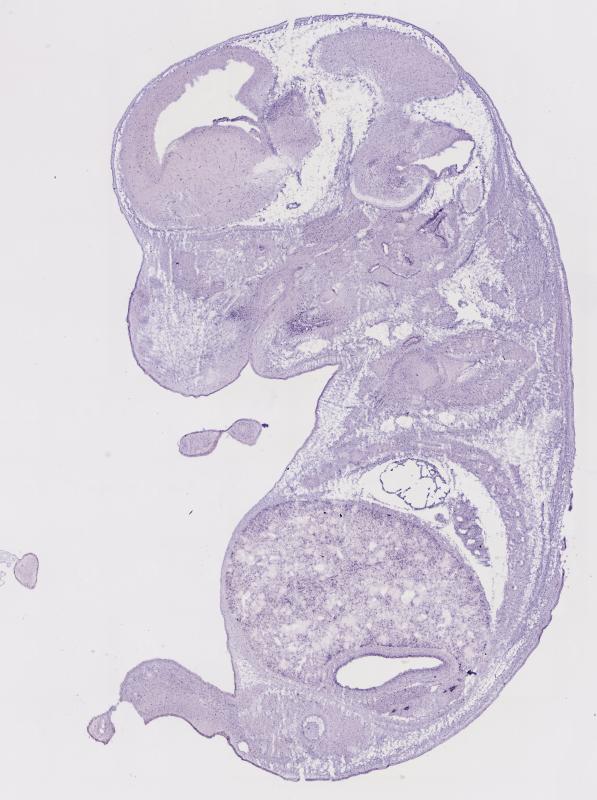

Homozygous mutation results in no dysmorphology or overt neurological problems. Homozygotes show no beta-mannosidase activity and display consistent cytoplasmic vacuolation in the central nervous system and minimal vacuolation in most visceral organs.

Expression

Expression Overview

early conceptus

embryo ectoderm

embryo endoderm

embryo mesoderm

embryo mesenchyme

extraembryonic component

alimentary system

auditory system

branchial arches

cardiovascular system

connective tissue

endocrine system

exocrine system

hemolymphoid system

integumental system

limbs

liver and biliary system

musculoskeletal system

nervous system

olfactory system

reproductive system

respiratory system

urinary system

visual system